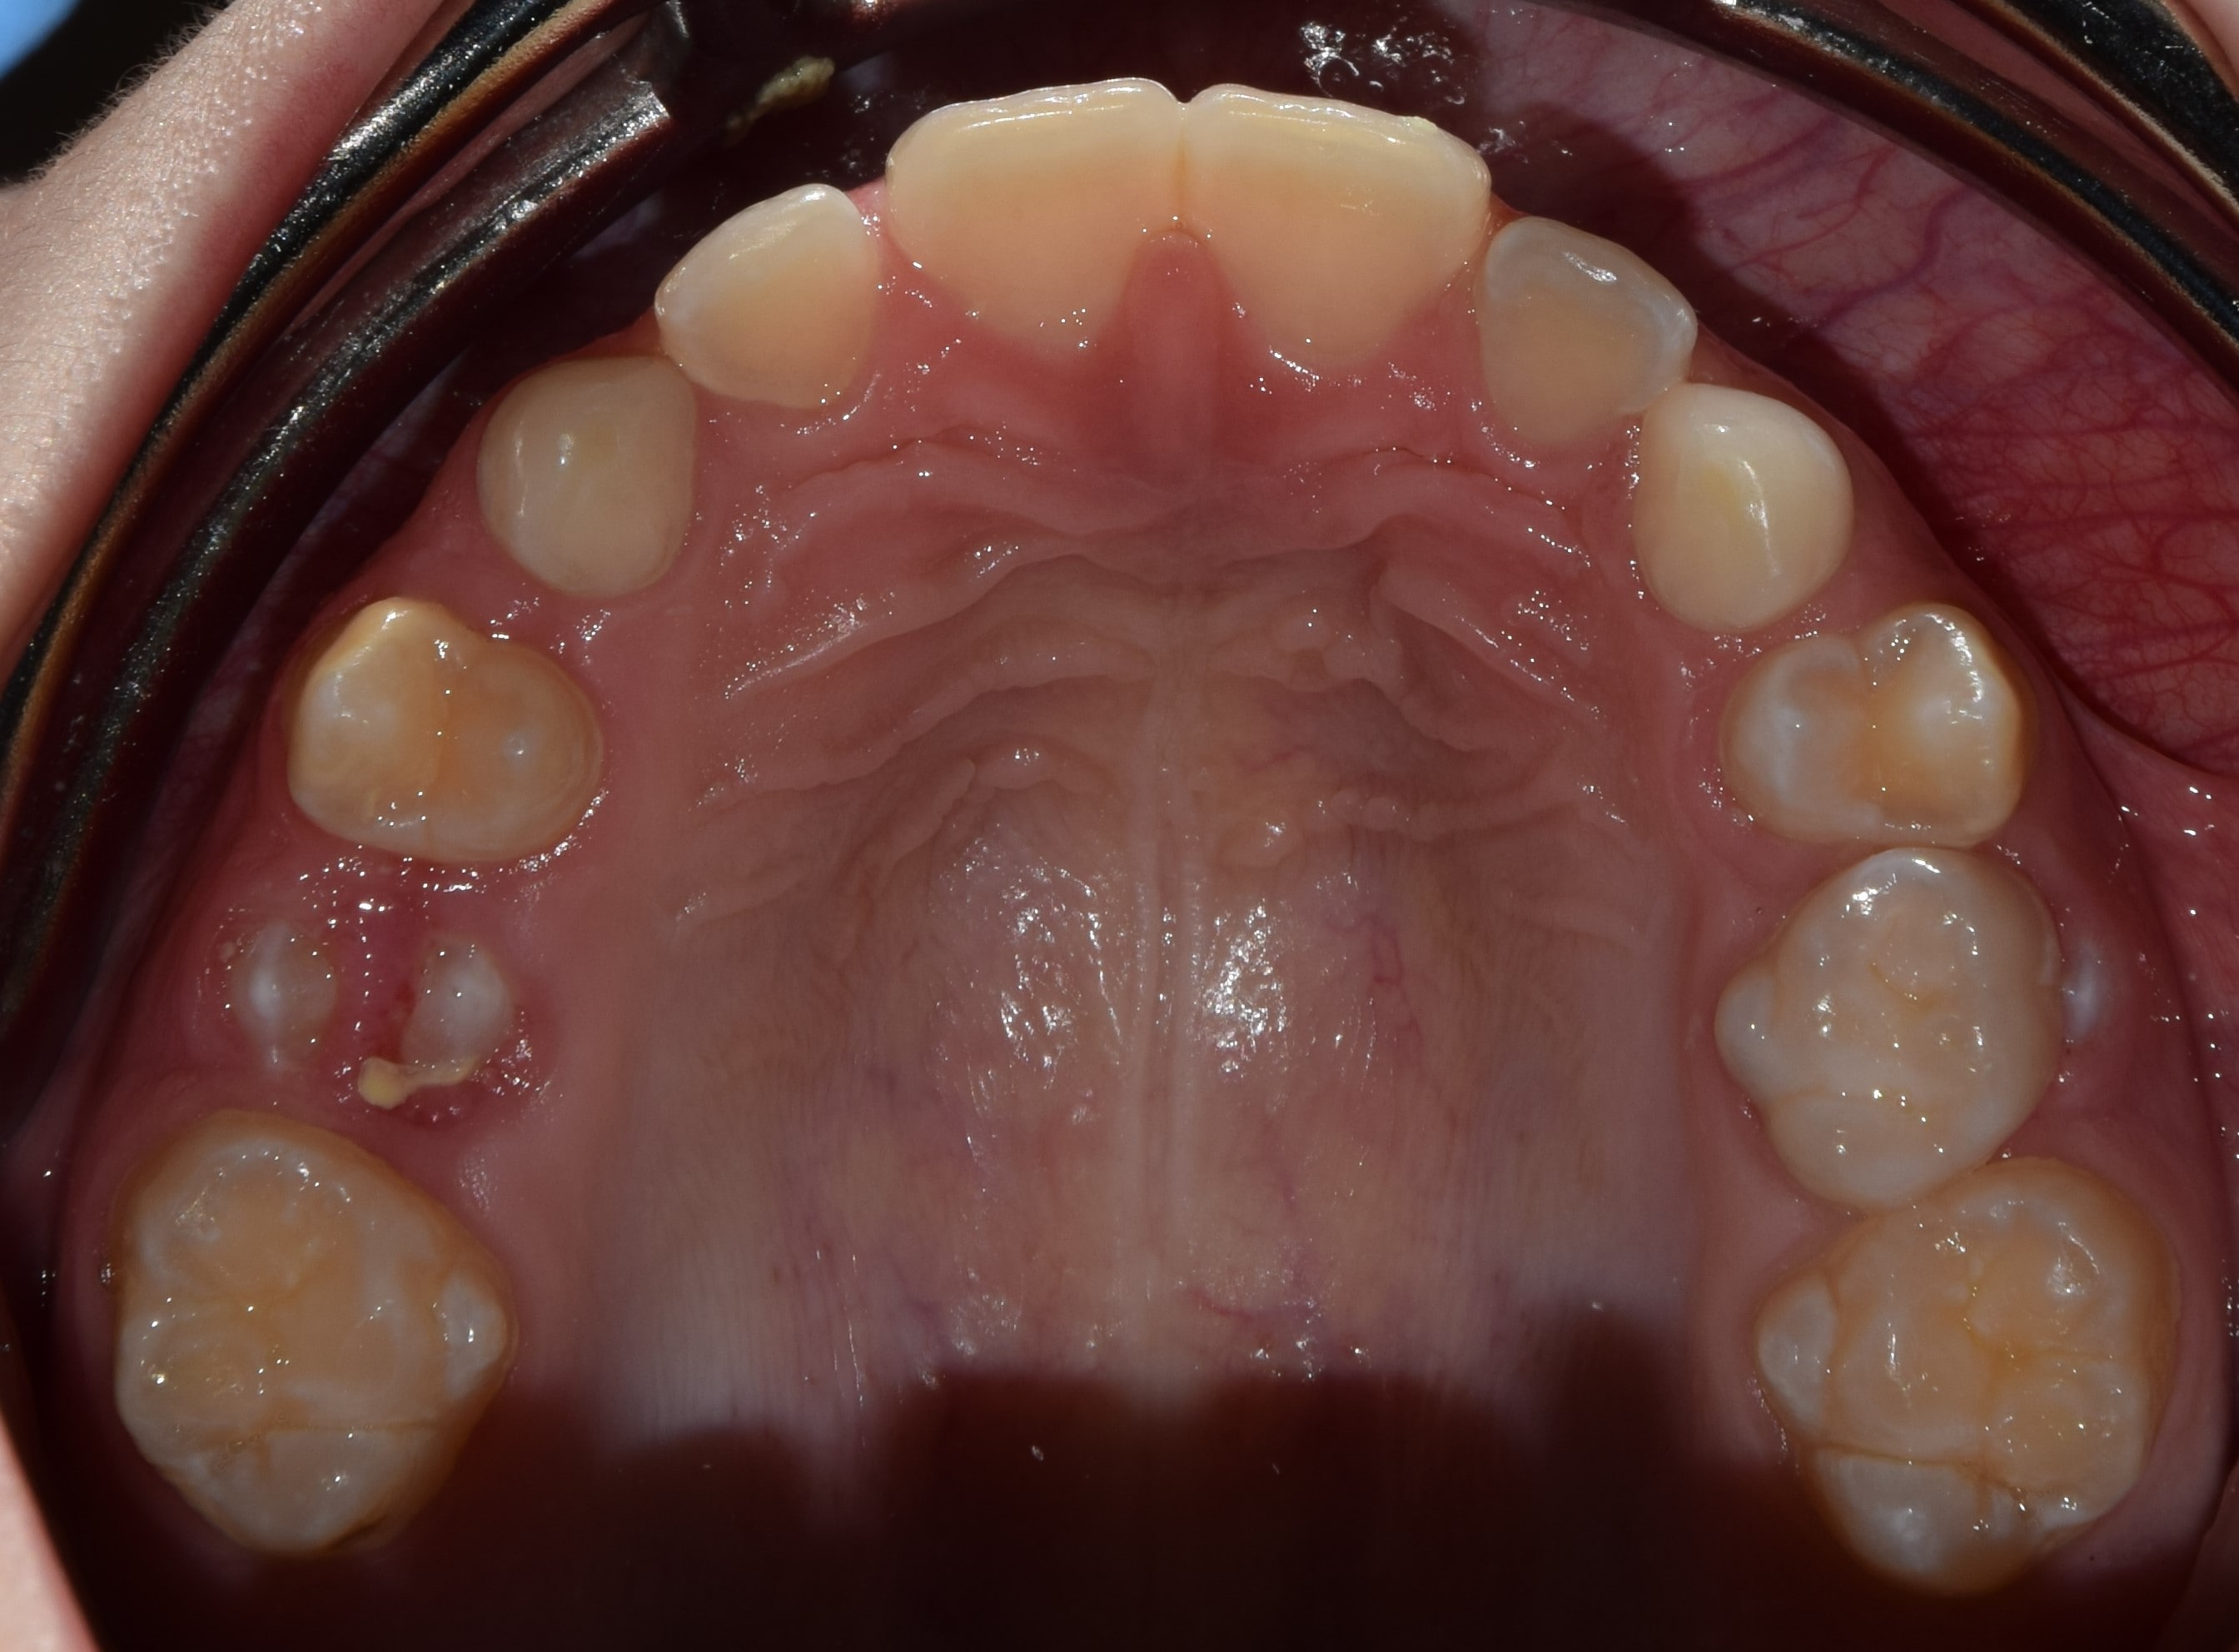

Maradó fogazat

Ideális esetben 32 fogból áll a maradó fogazat. A 32 fogat 4 negyedre (kvadránsra) osztjuk fel, jobb felső és bal felső, valamint bal alsó és jobb alsó. Tehát minden kvadránsban 8 fog található: 3db nagyőrlő, 2db kisőrlő, 1db szemfog és 2db metszőfog.